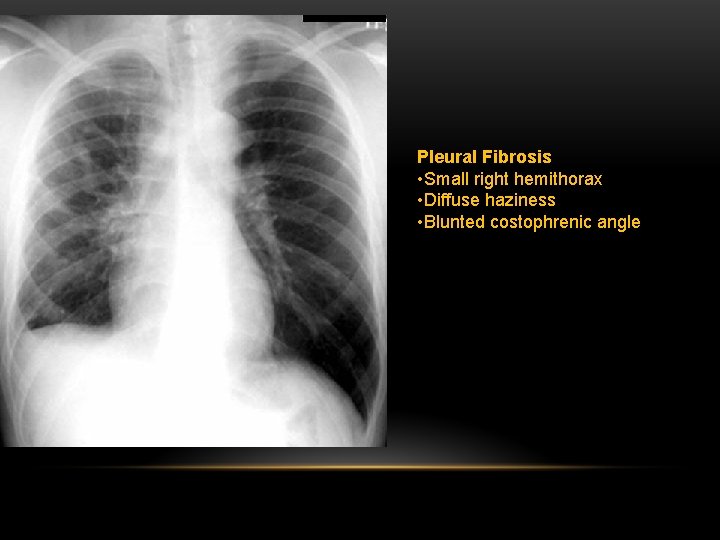

Pleural Fibrosis Diffuse haziness Apical cap thickening Blunting of costophrenic angle Loss of lung volume

Pleural Fibrosis • Small right hemithorax • Diffuse haziness • Blunted costophrenic angle